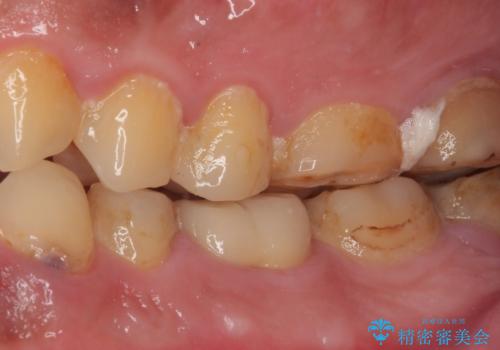

- 奥歯の歯肉から定期的に膿が出てくるとのことで来院された患者様です。

レントゲン写真などの診察を行った結果、根管治療が必要であったため、現在のクラウンを除去し、根管治療を行うこととしました。

根管治療後は症状を確認し、速やかにオールセラミッククラウンにて補綴治療を行うこととしました。

病変が消退しているかどうか、半年、1年とレントゲン写真で経過観察を行う必要があります。

4ヶ月後のレントゲンでは、病変の消退が認められました。